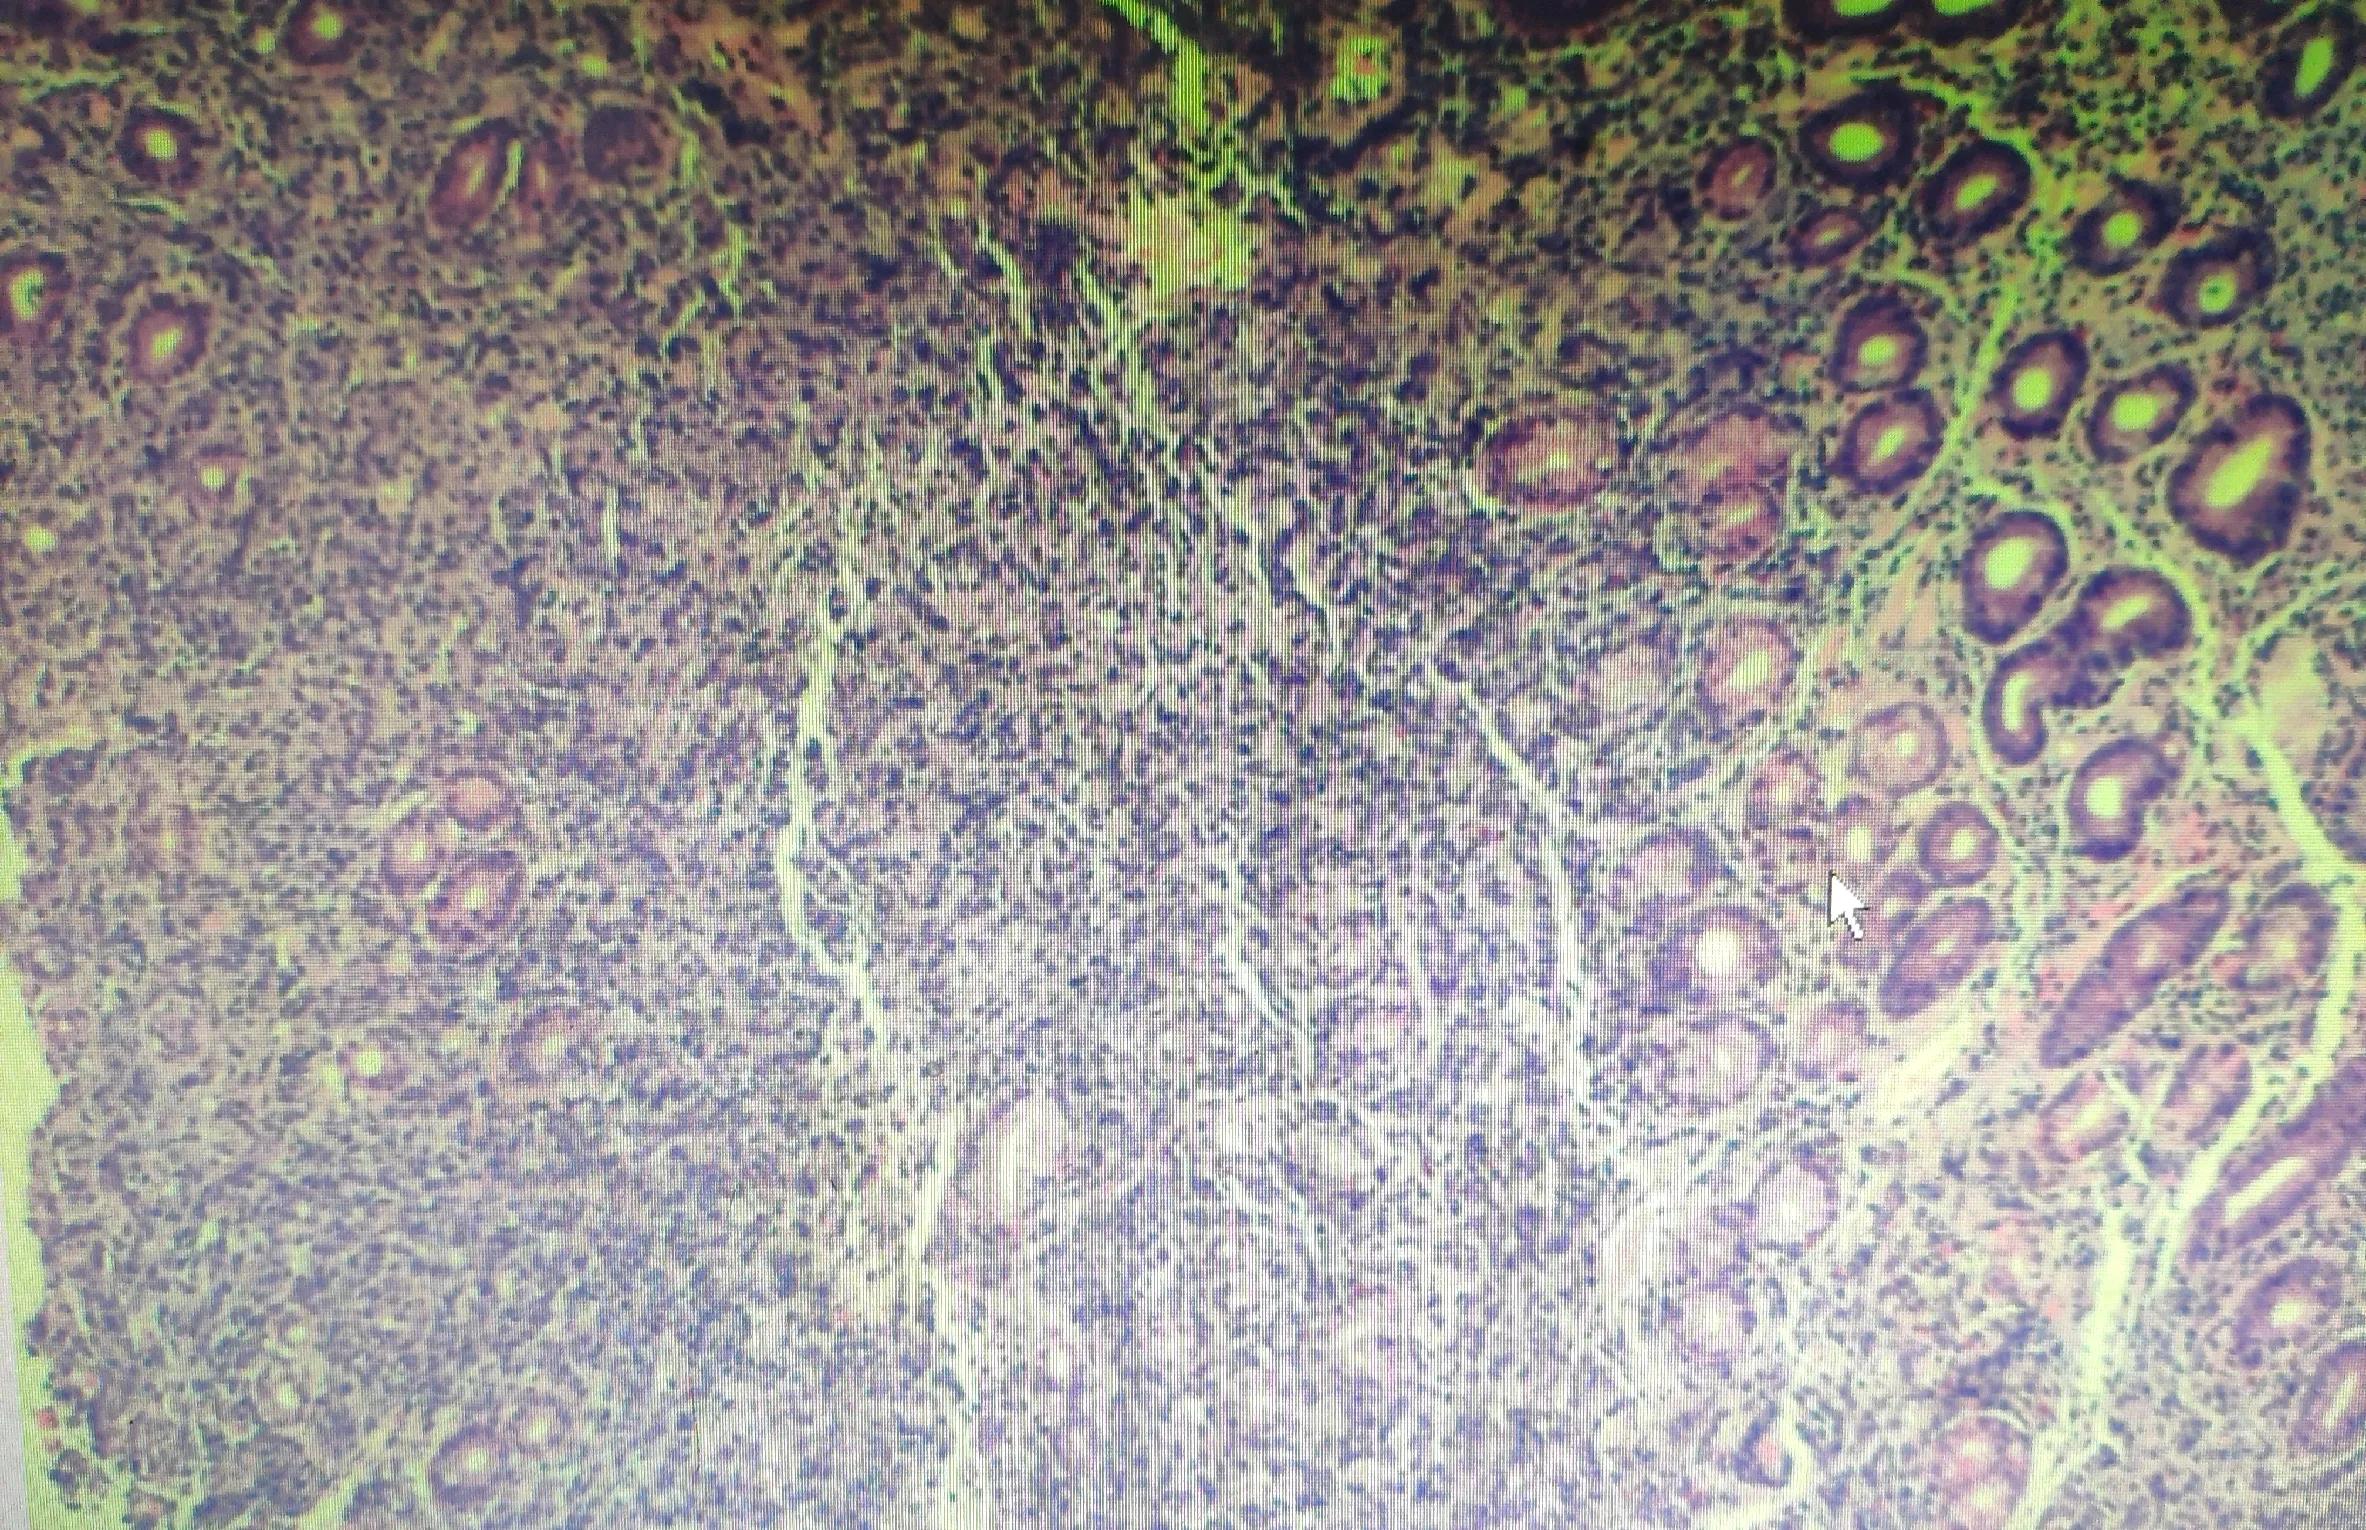

HE切片:胃体黏膜糜烂,间质中大量异形小圆形细胞浸润,部分呈巢状。

胃黏膜切片HE染色